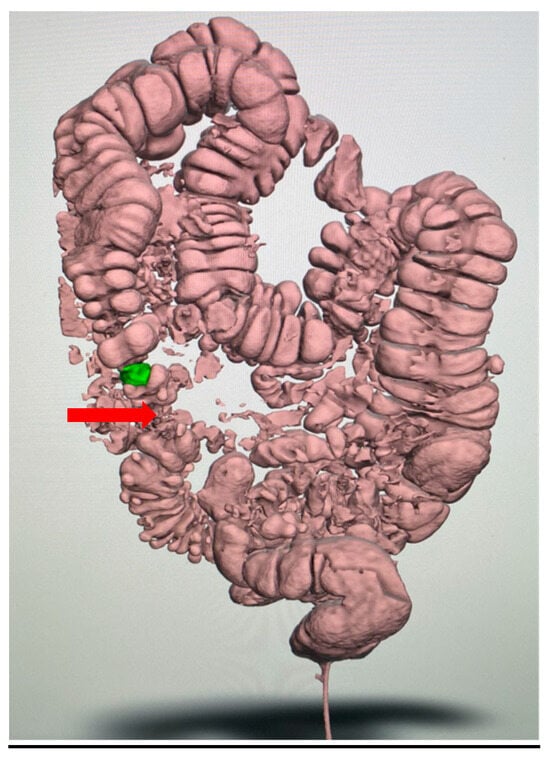

| Feature Evaluated | Virtual Colonoscopy Findings | 3D-Printed Model Findings |

|---|---|---|

| Extent of diverticulosis | Massive diverticulosis of sigmoid and descending colon | Same finding confirmed with clearer visualization of segmental involvement |

| Stenotic area | Suspected narrowing, poorly defined | Stenotic segment clearly delineated, with precise localization and extension |

| Anatomical relationships | Limited perception of spatial relations | Improved understanding of relationship between diseased colon and surrounding structures |

| Surgical planning implications | Suggestive of need for resection | Supported decision for left hemicolectomy |

| Tactile/spatial perception | 2D visualization only | Physical 3D model provided tactile and spatial feedback useful for team discussion and planning |